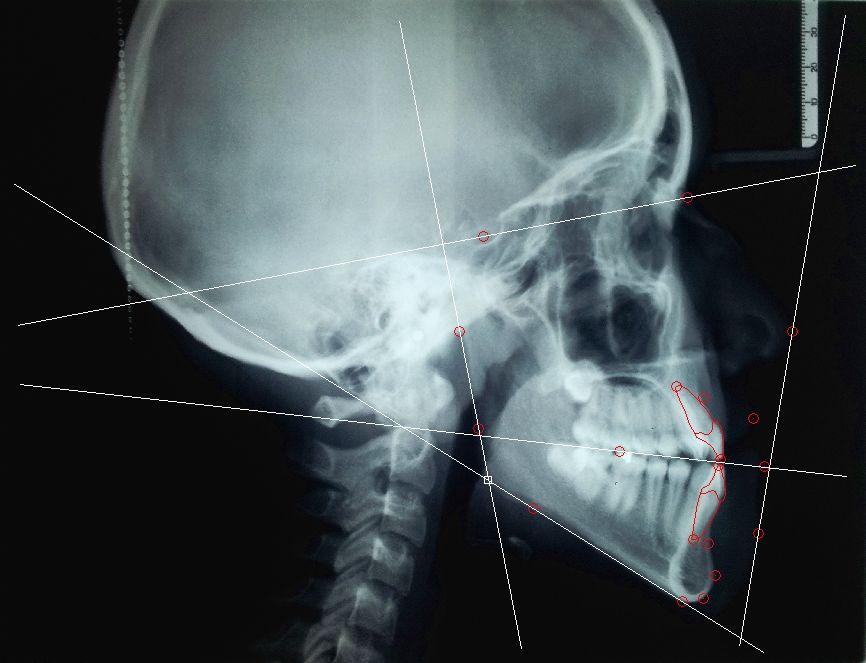

Concepto de Modelo de crecimiento

Dino Capelozza